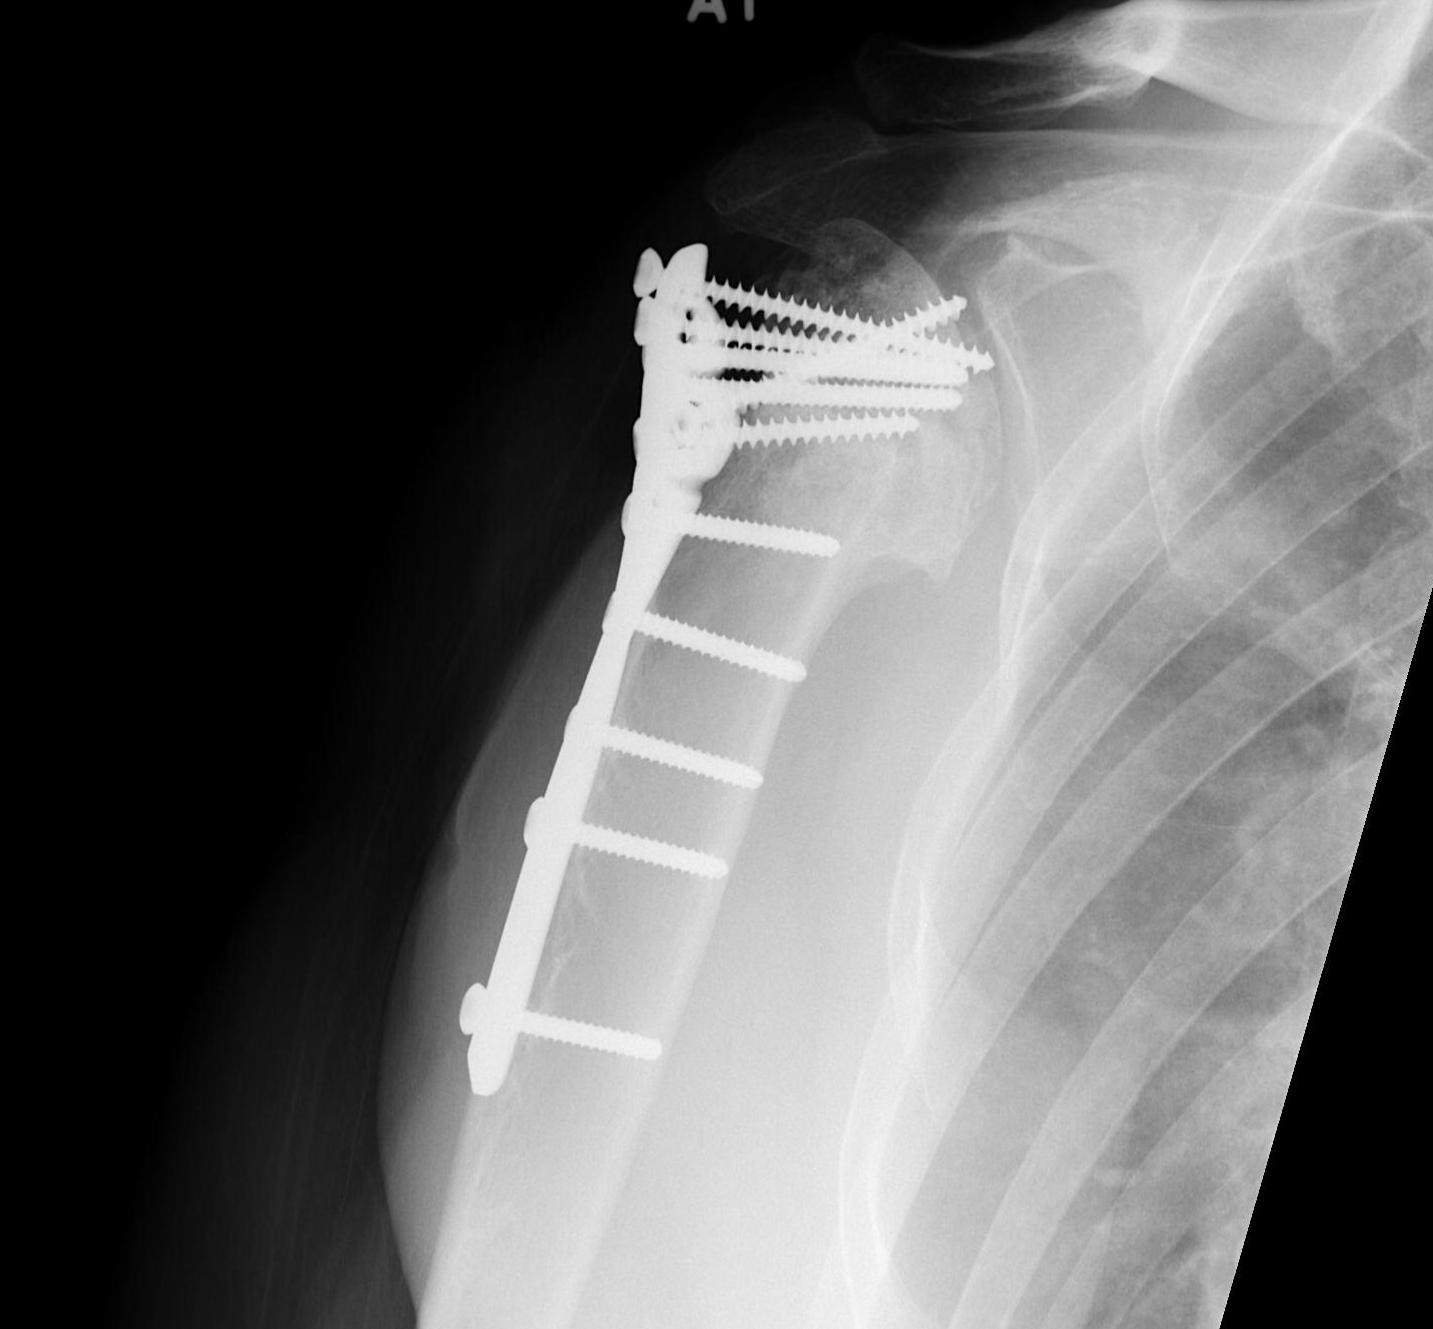

proximal humerus fracture Background ORIF with locking plate Arthroplasty Greater tuberosity fractures Lesser tuberosity fractures / avulsions Book traversal links for Proximal humerus fractures ‹ Pectoralis Major Tears Up Background ›